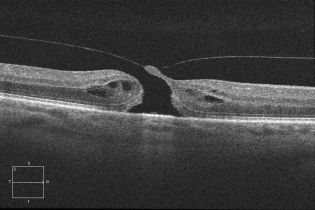

The macular hole on OCT shows partial or full thickness loss of retinal layers overlying the macular area, which may or may not be associated with a vitreomacular traction band.

The International Vitreomacular Traction Study (IVTS) classification scheme of vitreomacular traction and macular holes based on OCT findings:[55]

| Vitreomacular traction (VMT) | Distortion of foveal contour present or intraretinal structural changes in the absence of a full-thickness macular hole; size of attachment area between hyaloid and retina defined as focal if ≤ 1500 microns and broad if >1500 microns |

| Full-thickness macular hole (FTMH) | Full-thickness defect from the internal limiting membrane to the retinal pigment epithelium is described based on 3 factors:

1) Size -horizontal diameter at narrowest point: small (≤ 250 μm), medium (250-400 μm), large (> 400 μm) 2) Cause -primary or secondary 3) Presence or absence of VMT |